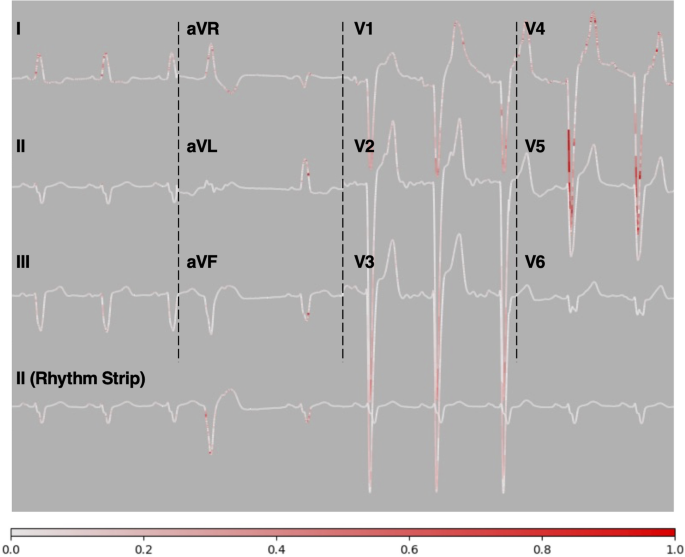

Figure 4 illustrates an example of local explanations for LVSD classification results obtained after tuning the ECG-FM using the SS-FF method. The DeepLIFT analysis showed that, across most leads, the QRS complex contributed most significantly to the model’s prediction, particularly in leads V1–V4, which reflect the septum and anterior wall of the left ventricle (LV). A notably strong contribution from the deep S wave was identified. Additionally, T wave contributions were prominent in leads V1–V4, indicating that ventricular repolarization characteristics (including shape and magnitude of the T wave) were important for LVSD prediction. Limb leads (I, II, III, aVR, aVL, aVF) occasionally showed significant QRS contributions, but the precordial leads (V1–V6), particularly V1–V4, consistently provided the highest contribution and thus had greater predictive importance.

Local explanation of the electrocardiographic (ECG) signal for left ventricular systolic dysfunction (LVSD) prediction using DeepLIFT. The areas highlighted in red indicate the parts of the ECG signal that contributed most to the model’s prediction. Each lead (I, II, III, aVR, aVL, aVF, V1-V6, and the rhythm strip) is displayed with intensity proportional to the importance of the segment to the prediction. The color bar at the bottom represents the magnitude of the contribution, with higher values indicating greater importance.